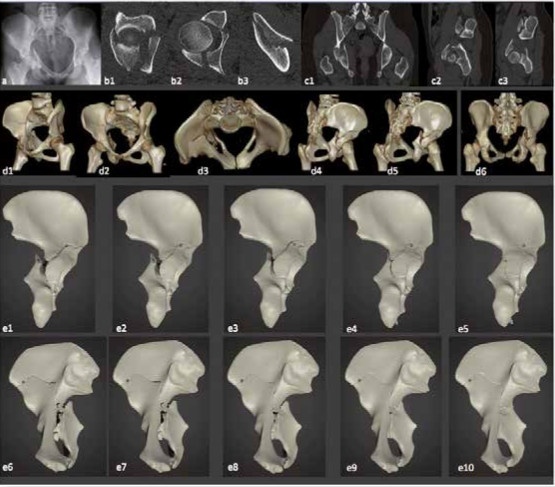

A: herkömmliche Röntgentechnik, b1-b3: CT (seit 1973 möglich), c1-c3: Multiplanare Rekonstruktion (seit 1993 möglich), d1-d6: 3D-Rekonstruktion

(seit 1993 etabliert), e1-e10: 3D-Druck (seit ca. 2013 in der Unfallchirurgie); Animation der Reposition durch komplexe Slicing Software

und Unity 3D-Software (seit 2017/2018 ist die Darstellung für den Nutzer auch als Video möglich) (Bilder: C. Willy, Berlin)